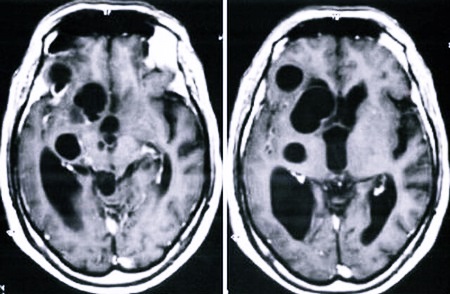

Считается, что четыре из пяти полостных ликворных образований ничем не угрожают человеку. Они никак не проявляются и практически не растут. Кисты в большинстве случаев находят случайно, при проведении МРТ. Вмешательство хирурга при таком развитии новообразования не требуется.

Иногда такие внутричерепные аномалии могут вести себя агрессивно. Чаще всего это те нарушения, которые развиваются по второму типу. Быстро растут кисты после полученного сотрясения мозга, воспалительного процесса. Они могут достигать внушительных габаритов.

Если киста растет, она начинает давить на ткани мозга. Это провоцирует боль и функциональные расстройства. Очень опасно то, что нарушается кровообращение, дыхательный рефлекс. Это ведет к необратимым последствиям и омертвению тканей. Со временем, если новообразование ведет себя агрессивно, не замедляет свой рост, появляются неврологические расстройства. Могут наблюдаться судороги, частичный или полный паралич. Как следствие – такое состояние может привести к инвалидности. Жить с такими кистами нельзя, их нужно лечить.

Самое опасное – разрыв тканей кисты. Внутрь черепа попадает экссудат. Результат – сильнейшая интоксикация и гибель больного. Если уплотнение достигло крупных размеров, полость удаляют или ставят дренаж.